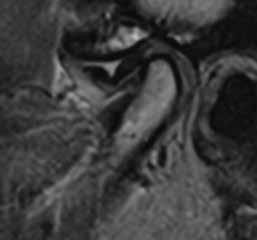

Magnetic resonance imaging (MRI) has been a staple in medicine and dentistry for many years. In dentistry, it serves a somewhat confined role in imaging the temporomandibular joints (TMJ) and occasionally the head and neck, including cysts or tumors. Dental MRI research and publications on these indications, as well as more “traditional” dental imaging tasks such as caries or periapical lesion detection, have progressed steadily since the mid-1980s, followed by a rapid increase in published papers in the early 2020s. These studies have long demonstrated the utility of MRI TMJ and cyst/tumor imaging, as well as the promise of MRI for essentially the entire range of dental imaging indications. Indications include caries, periapical disease, periodontal disease, growth and development/

Proton density image of TMJ demonstrating anterior disc displacement, disc fold and joint effusion.